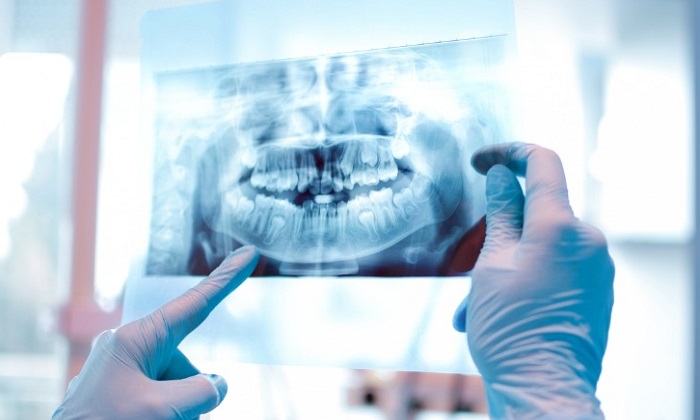

مرحله دوم: عکسبرداری از دندانها

پس از بررسیهای اولیه، ارتودنتیست از بیمار میخواهد که یک عکس کامل از دندانهایش تهیه کنید. اگر تنها چند دندان دچار ناهنجاری باشند، ممکن است پزشک متخصص تنها عکسبرداری از آنها را تجویز کند.

مرحله سوم: بررسی عکس دندانها

در این مرحله پزشک بهدقت عکس دندانها را بررسی میکند و درباره مشکلات فک و روشهای درمانی که برای ناهنجاریهای دندانها وجود دارد به بیمار مشاوره میدهد. همچنین سلامت دهان و دندان بیمار هم مورد بررسی قرار میگیرد و در صورت بروز مشکل برای لثهها یا خرابی دندانها، متخصص ارتودنسی بیمار را برای رفع آنها نزد دندانپزشک ارجاع میدهد.